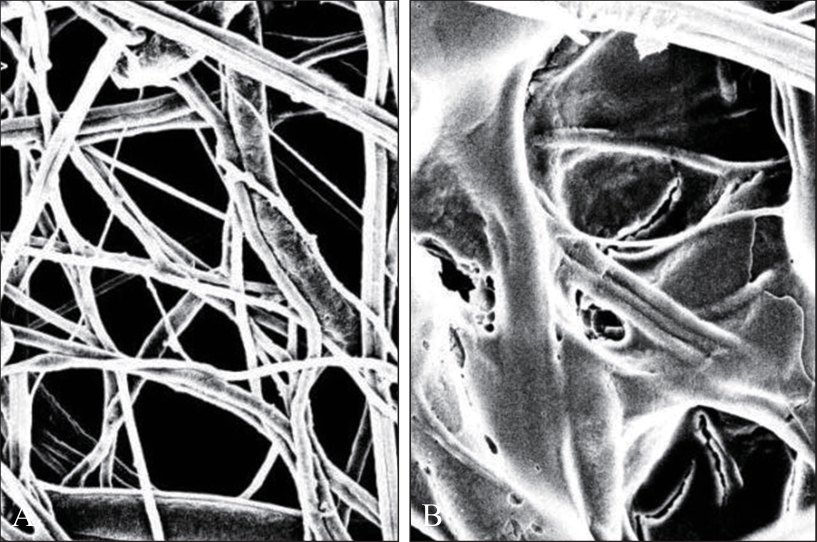

目的 探究负载了血小板浓缩生长因子(CGF)的聚己内酯(PCL)—聚乙二醇(PEG)支架对人牙周膜干细胞(hPDLSCs)黏附、增殖及成骨分化能力的影响。 方法 通过浸入及冻干法制备PCL-PEG-CGF复合支架,观察复合支架的显微结构并检测其机械性能及生物相容性。酶消化法培养hPDLSCs,并通过流式细胞术鉴定hPDLSCs。选取第三代hPDLSCs,分别通过CCK-8实验、4’,6-二脒基-2-苯基吲哚(DAPI)染色、碱性磷酸酶(ALP)染色、茜素红染色及Western blot实验检测PCL-PEG-CGF复合支架对hPDLSCs黏附、增殖及成骨分化能力的影响及成骨相关蛋白[Runt相关转录因子2(Runx2)、ALP、骨形态发生蛋白2(BMP2)]的表达情况。 结果 PCL-PEG-CGF复合支架在扫描电镜下呈孔隙大小不等的蜂窝状结构,其亲水性6 s时θ角接近0°,弹性模量为(4.590 0±0.149 3)MPa,其亲水性、断裂拉伸强度及断裂延伸率均与PCL-PEG支架相似;hPDLSCs在PCL-PEG-CGF复合支架上的黏附能力明显优于PCL-PEG支架(P<0.01),与对照组相比,第3、5、7天时各实验组的hPDLSCs增殖速率显著增加(P<0.01),且PCL-PEG-CGF复合支架与其余组间差异有统计学意义(P<0.01);PCL-PEG-CGF复合支架组ALP活性明显升高(P<0.05),矿化结节数量明显增加及成骨相关蛋白(Runx2、BMP2、ALP)的表达均明显增强(P<0.05)。 结论 PCL-PEG-CGF复合支架具有较好的机械性能及生物相容性,可促进hPDLSCs黏附及增殖,并通过增强成骨相关蛋白的表达促进hPDLSCs的成骨分化能力。

Objective This study investigated the effects of a polycaprolactone (PCL)-polyethylene glycol (PEG) scaffold incorporated with concentrated growth factor (CGF) on the adhesion, proliferation, and osteogenic differentiation of human periodontal ligament stem cells (hPDLSCs). Methods The PCL-PEG-CGF composite scaffold was fabricated using an immersion and freeze-drying technique. Its microstructure, mechanical properties, and biocompatibility were systematically characterized. The hPDLSCs were isolated through enzymatic digestion, and the hPDLSCs were identified through flow cytometry. Third-passage hPDLSCs were seeded onto the composite scaffolds, and their adhesion, proliferation and osteogenic differentiation were assessed using CCK-8 assays, 4’,6-diamidino-2-phenylindole (DAPI) staining, alkaline phosphatase (ALP) staining, alizarin red staining, and Western blot analysis of osteogenesis-related proteins [Runt-related transcription factor 2 (Runx2), ALP, and morphogenetic protein 2 (BMP2)]. Results Scanning electron microscopy revealed that the PCL-PEG-CGF composite scaffold exhibited a honeycomb-like structure with heterogeneous pore sizes. The composite scaffold exhibited excellent hydrophilicity, as evidenced by a contact angle (θ) approaching 0° within 6 s. Its elastic modulus was measured at (4.590 0±0.149 3) MPa, with comparable hydrophilicity, fracture tensile strength, and fracture elongation to PCL-PEG scaffold. The hPDLSCs exhibited significantly improved adhesion to the PCL-PEG-CGF composite scaffold compared with the PCL-PEG scaffold (P<0.01). Additionally, cell proliferation was markedly improved in all the experimental groups on days 3, 5, and 7 (P<0.01), and statistically significant differences were found between the PCL-PEG-CGF group and other groups (P<0.01). The PCL-PEG-CGF group showed significantly elevated ALP activity (P<0.05), increased mineralization nodule formation, and upregulated expression of osteogenic-related proteins (Runx2, BMP2 and ALP; P<0.05). Conclusion The PCL-PEG-CGF composite scaffold exhibited excellent mechanical properties and biocompatibility, enhancing the adhesion and proliferation of hPDLSCs and promoting their osteogenic differentiation by upregulating osteogenic-related proteins.